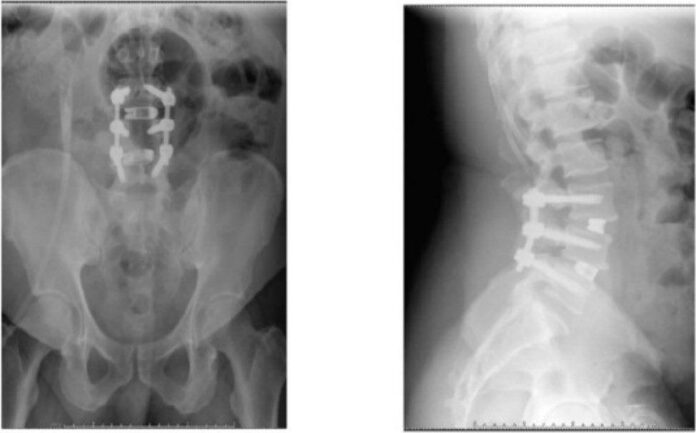

劉彥麟進一步說明,該名病患因為脊椎不穩定而且神經壓迫嚴重,因此選擇椎弓鋼釘置入、完整減壓及脊椎內支架來達到穩定脊椎及神經放鬆的效果,術後第三天即可下床走路,一個禮拜後回家休養,叮嚀照顧好傷口及穿戴護腰保護開刀處,適當的休息,幾個月後成功擺脫神經壓迫造成的麻木痠痛,獲得一個新的人生。

術後照—椎弓鋼釘置入、減壓及支架置入 (圖片來源為國際外科雜誌) |

※圖片來源:Jonathan McKeeman, Emily Zielinski, Flynn A. Rowan, L3-L4/L4-L5 Type II-A spondylolisthesis: A case report, International Journal of Surgery Case Reports, Volume 124, 2024,